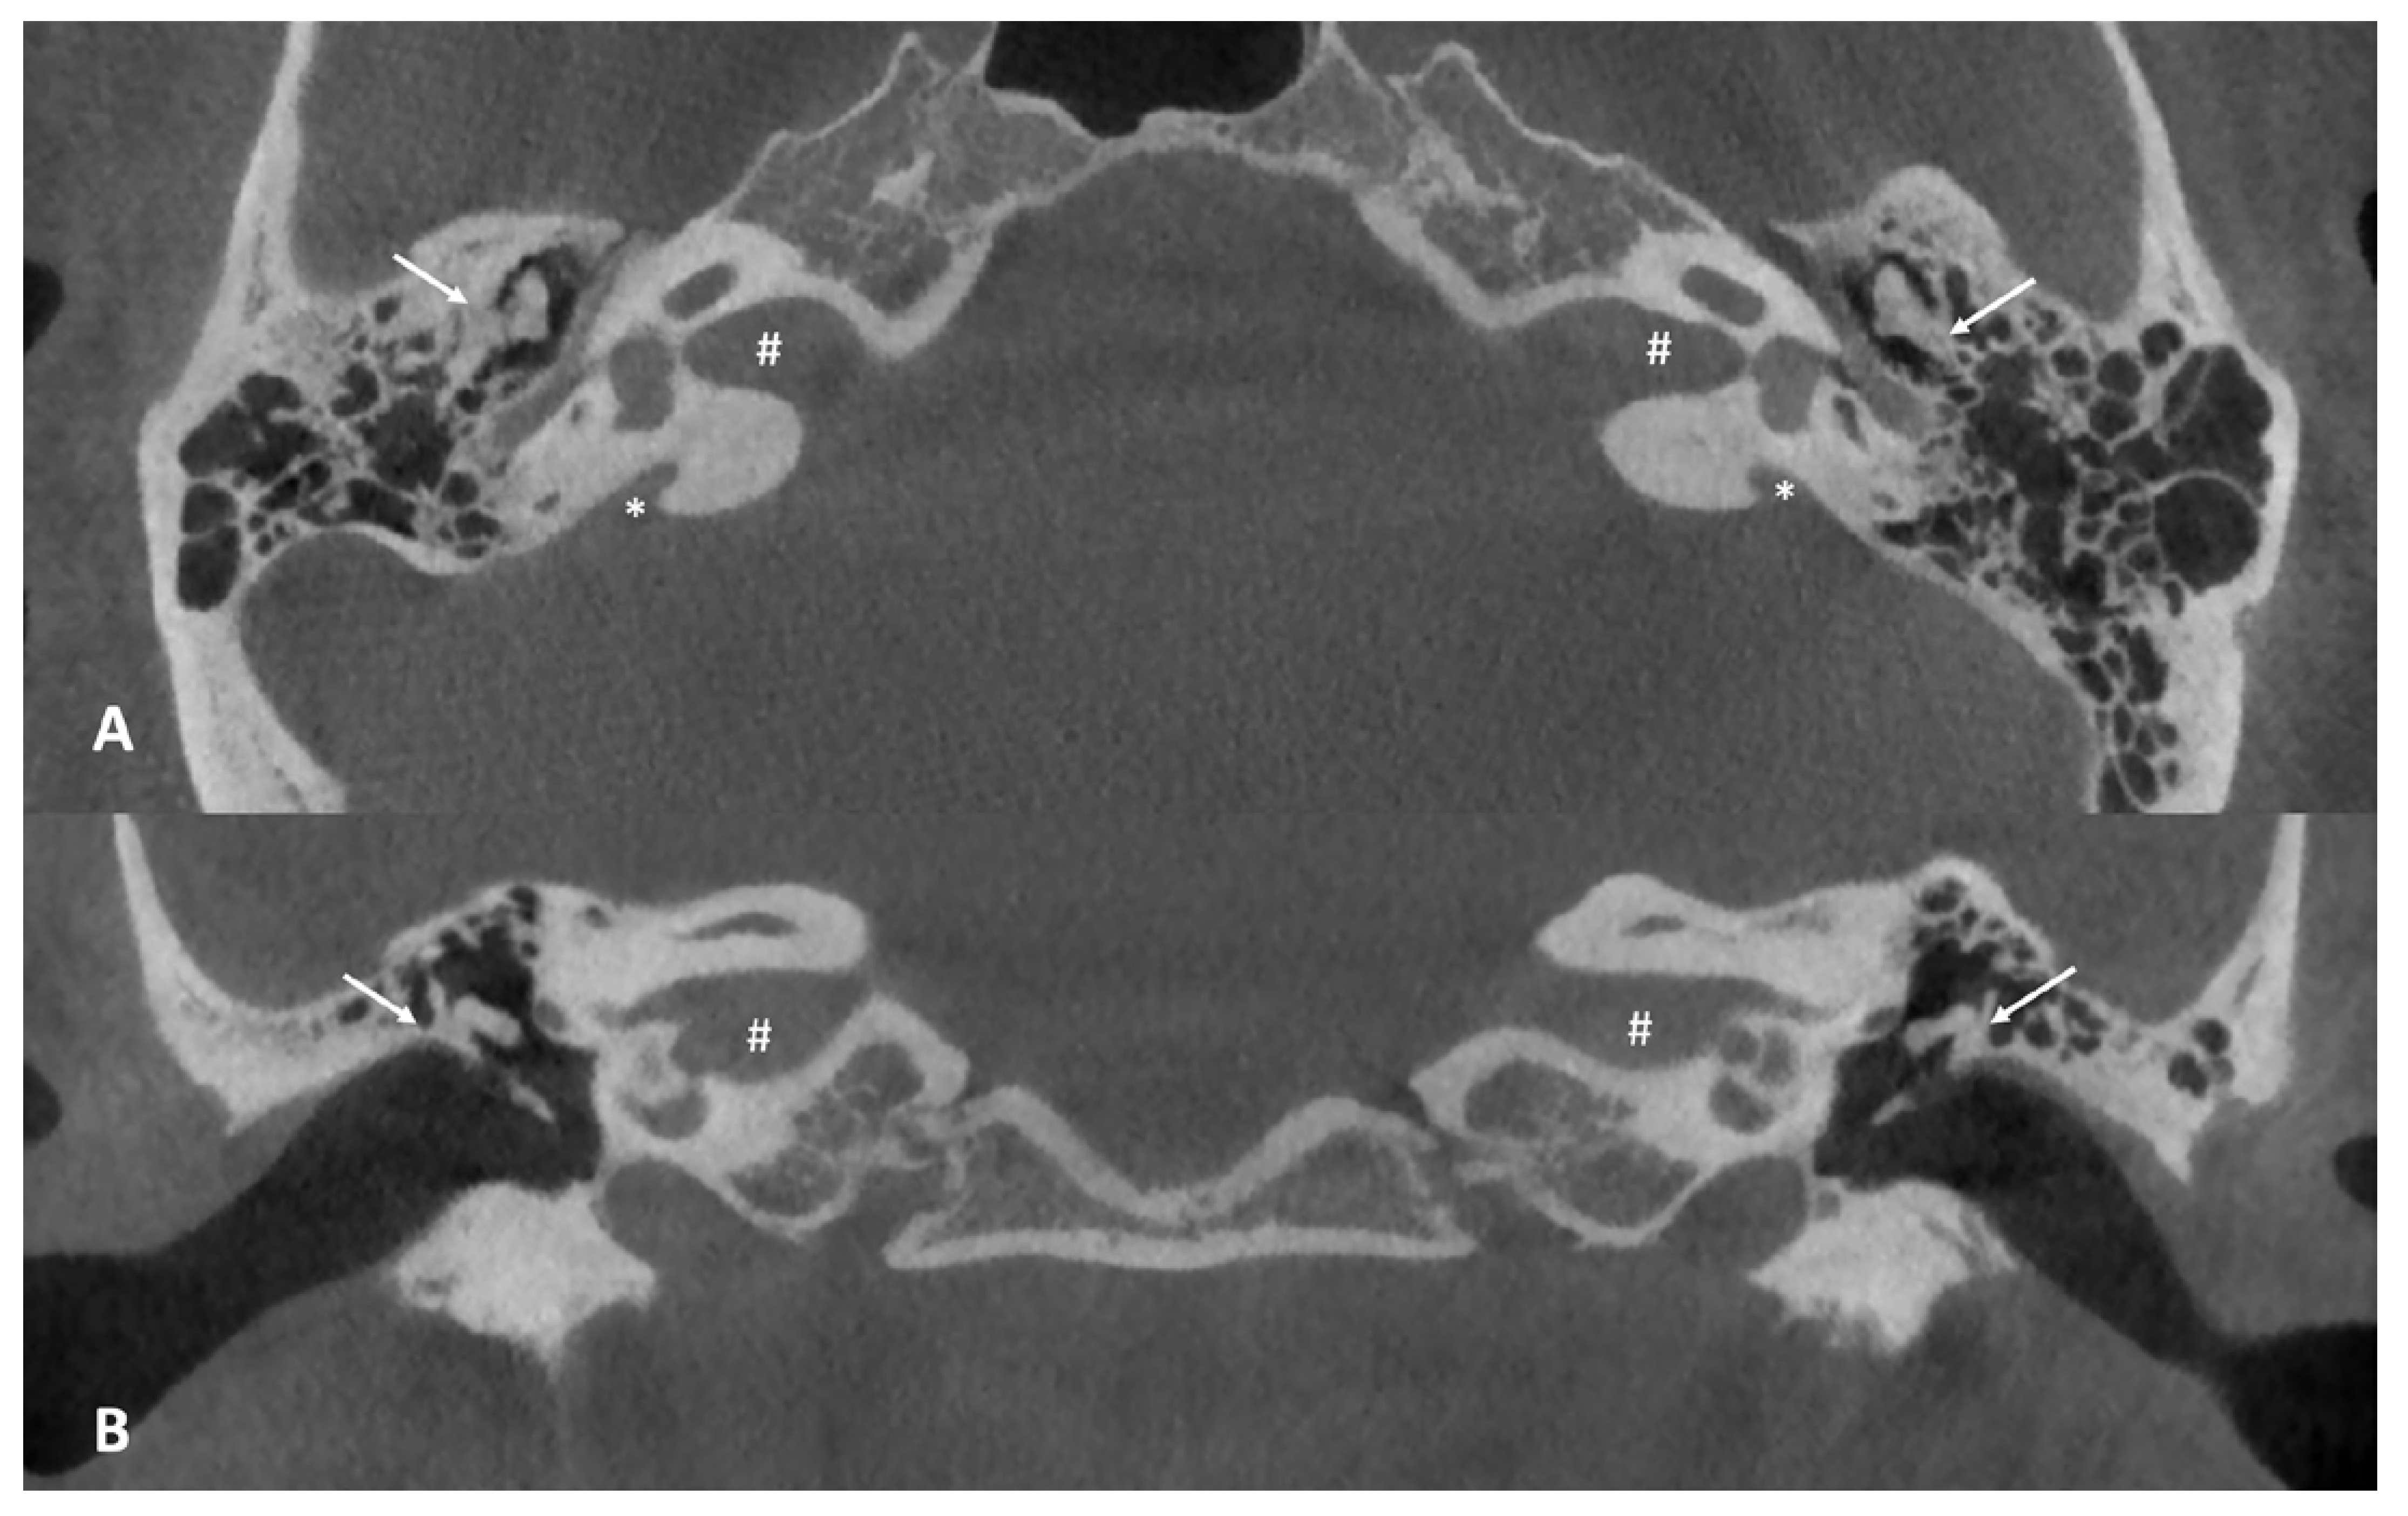

At this point, the patient was referred to our center to obtain a second opinion, given the unsatisfactory hearing improvement after surgery. A cone beam computed tomography (CBCT) of the temporal bone was performed, revealing bilateral enlarged vestibular aqueducts (EVAs) associated with a malformation of the ossicular chain, which appeared bilaterally fixed to the upper lateral wall of the middle ear (Figure 2). The vestibular aqueduct diameter at the midpoint resulted to be 1.74 mm on the right and 2.45 mm on the left.

Figure 2.

(A) Axial cone beam CT scan of the temporal bone. Note the abnormal anatomy of the middle ear, with the ossicular chain almost “fused” with the lateral wall of the tympanic cavity (white arrows) and the enlarged vestibular aqueduct on both sides (white asterisks), 1.74 mm on the right and 2.45 mm on the left. (B) Coronal cone beam CT scan of the temporal bone. Note the fusion of the incus to the lateral wall of the tympanic cavity (white arrows). The white hash (#) found in both axial and coronal images, identifies the internal auditory canal.